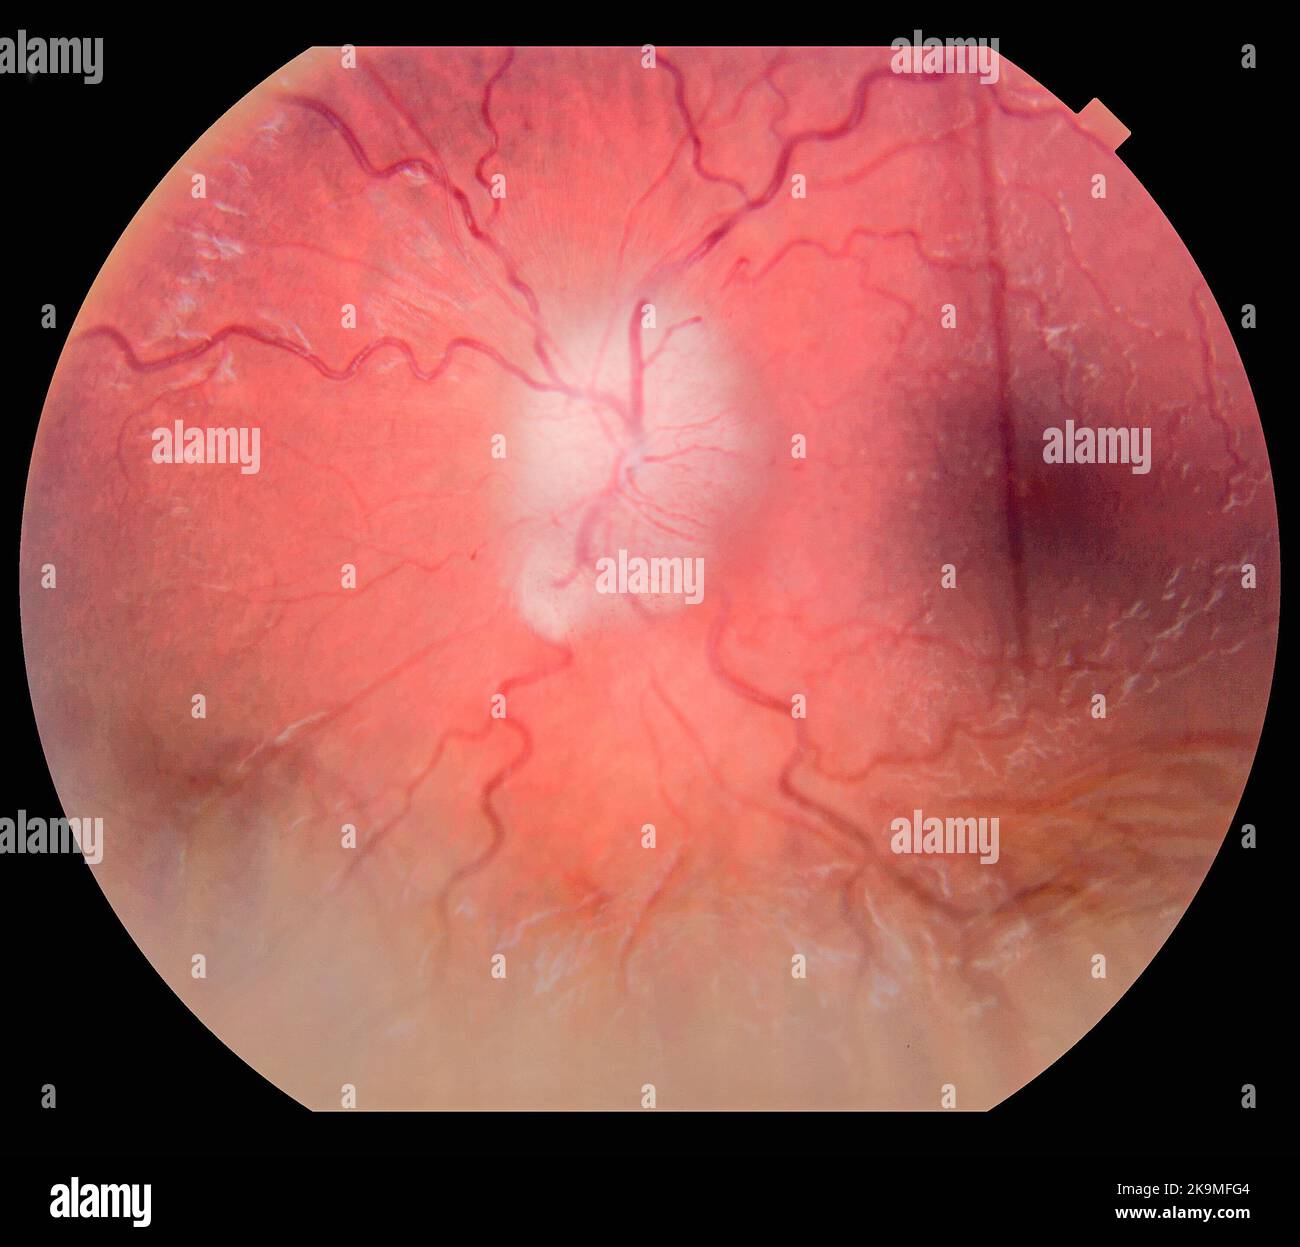

Photography of Human Eye Retina Stock Photohttps://www.alamy.com/image-license-details/?v=1https://www.alamy.com/photography-of-human-eye-retina-image487873457.html

Photography of Human Eye Retina Stock Photohttps://www.alamy.com/image-license-details/?v=1https://www.alamy.com/photography-of-human-eye-retina-image487873457.htmlRF2K9MFG1–Photography of Human Eye Retina